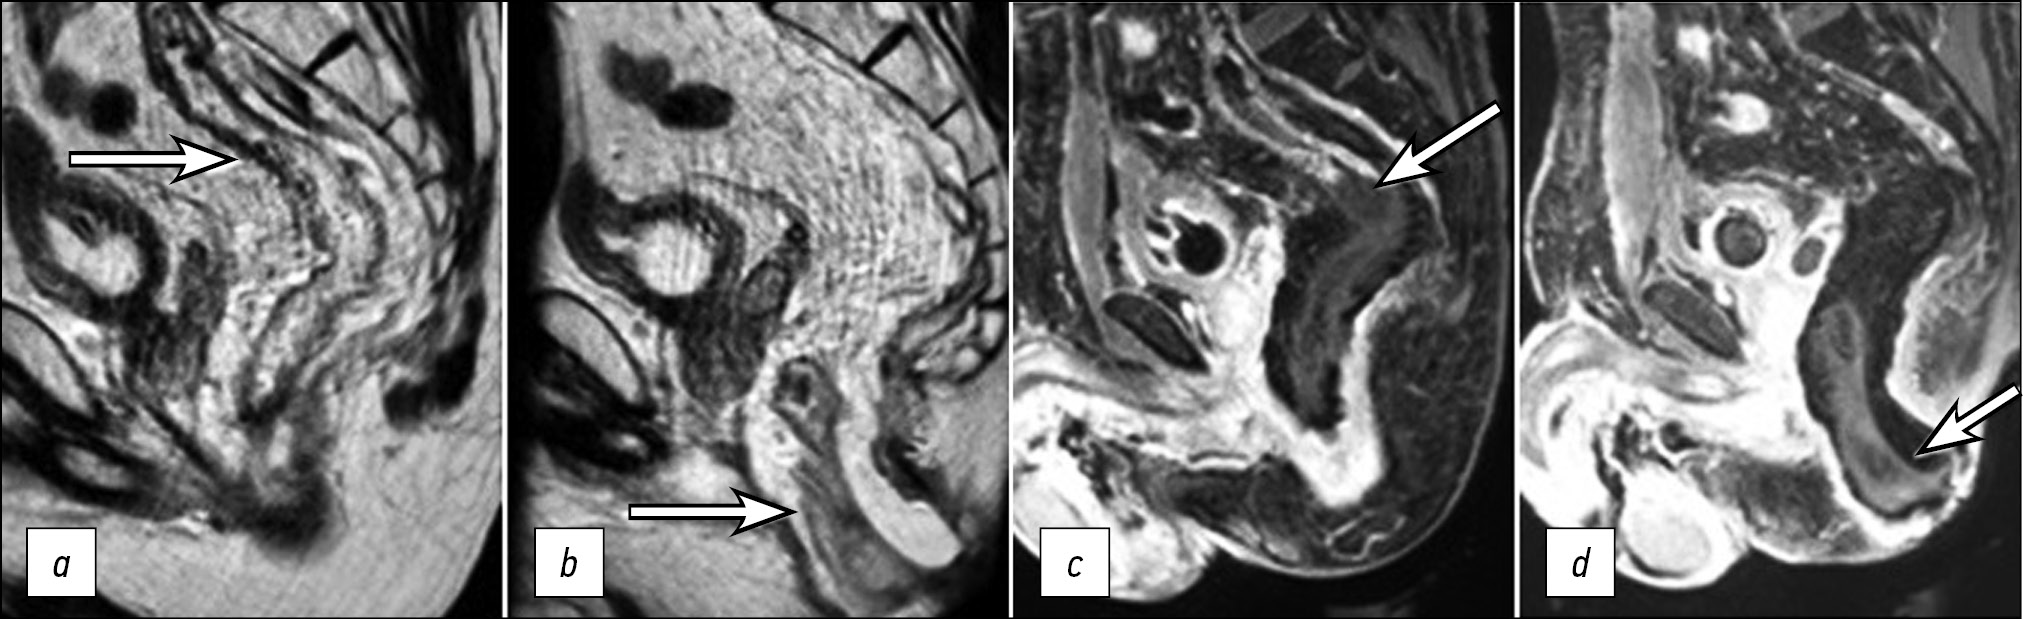

Intermittent low-grade fever and a high serum C-reactive protein (CRP) level were detected starting on postoperative day (POD) 1 (Fig. 1). Due to this clinical pattern, imaging studies, including MRI and rectoscopy, were performed on POD 3. Pelvic MRI included high-resolution T2-weighed images (WIs) in three orthogonal planes and T1WIs with fat suppression and intravenous gadolinium enhancement. Diffuse edema was present on the wall of the colon 15 cm proximal to the coloanal anastomosis, with sharply reduced contrast uptake, which was interpreted as a disturbance in blood supply in the pulled-through distal colon segment (Fig. 2). The pulled-through colon mucosa was pink on rectoscopy, with no signs of ischemia or necrosis; mucus was in the lumen.

Figure 2. MRI scans of two adjacent sagittal sections of the pelvis in Т2 mode (a, b) and 1-FS mode with contrast enhancement (c, d) on POD 3: the upper (a, c) and lower (b, d) segments of the pulled-through colon with thickened walls and sharply reduced contrast uptake, 15 cm long, with a distinct boundary between the ischemic and normal colon segments (arrows).

In our clinical case, the signs of ischemia in the pulled-through colon segment, which was detected by MRI on POD 3, included nonspecific manifestations of non-enhanced T2-WIs in the form of edema and thickening of the colon wall, as well as the absence of contrast uptake above the anastomosis with a distinct upper boundary on the post-contrast images. The involvement of a significant area (6–15 cm) from the anastomosis level is a characteristic feature of this type of colonic ischemia [5], which we also observed in our patient.